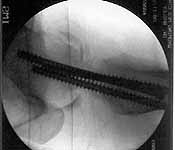

30 y/o man in head-on MVA 12/22/03 sustaining grade II open left femoral midshaft fracture (treated with appropriate staged debridement and retrograde statically locked IM nail), left lateral split tibial plateau fracture (treated with reduction and percutaneous cannulated screw fixation) and comminuted left femoral neck fracture (treated with open reduction and non-compression screw fixation). All initial treatment at another institution and patient recently came to me for follow-up care (he was travelling out of town when he was injured). He has a large (7cm) defect of lateral half of femoral shaft fracture which I plan to pack with a ton of bone graft next week (open fracture site soft tissues healed nicely without sign of infection).

Some additional information. Initial neck treatment was open through lateral

incision with anterior exposure of the fracture. Op note mentions that intra-op

reduction of neck was suboptimal due to comminution, but makes no mention of

state of capsule and I haven't yet been able to speak directly with the treating

surgeon. Attached are intra-op films of neck and films of shaft (not great,

but show the cortical defect). Any further input is invited and welcome.